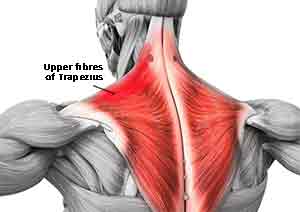

This is pain on the top of the shoulders. The Trapezius muscle is very tight and will ache and give tension all the way up the neck and down into the upper ribcage. Trapezius frequently contributes to headaches when they are tense (hypertonic).

Case: A late middle aged man consulted me for headaches. He had been suffering since he was a teenager with debilitating pain. He had been having treatment from an Osteopath for many years. I found that the upper fibres of his Trapezius were very tense and fibrotic. He also had a mis-alignment of this Atlas vertebrae and of C-5-6. I treated these areas giving vertebral manipulation and specialized muscle technique. His improvement was immediate and in the following weeks exhibited little or no symptoms. Now, three years later he has maintained this improvement.